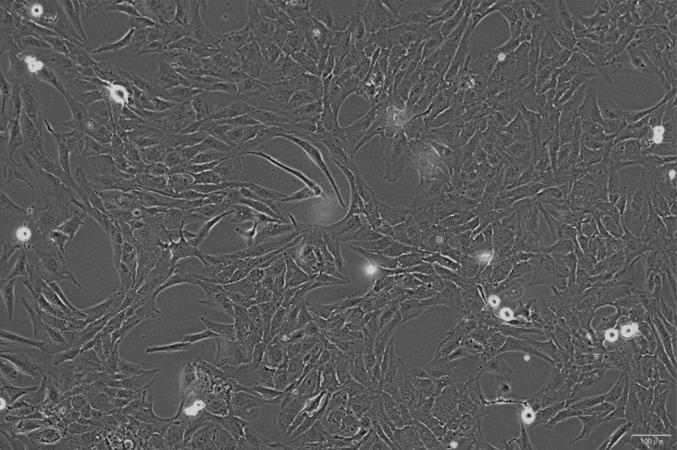

人非小细胞肺癌细胞系(A549)是 1972 由 D·J·Griad 等人取自一名 58 岁的白人男性的肺癌组织,通过组织移植培养建系。该细胞角蛋白染色呈阳性,可通过胞苷二磷酸胆碱途径合成高比例的不饱和脂肪酸卵磷脂,这对细胞膜磷脂的维持至关重要。

人非小细胞肺癌细胞系(A549)常用于细胞凋亡、非小细胞肺癌、肺肿瘤、细胞周期的研究。

贴壁生长;上皮细胞样 |